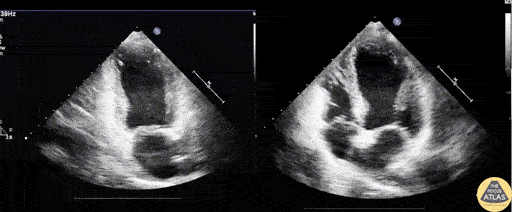

A 50 year old male with community acquired pneumonia presented to the ED with worsening symptoms, abnormal EKG, and elevated troponin without an obstructing lesion on cath. Bedside echo revealed akinesia of the entire mid and apical left ventricle indicative of Takotsubo cardiomyopathy on apical 2 chamber (left) and apical 4 chamber (right) views. Image courtesy of Robert Jones DO, FACEP @RJonesSonoEM Director, Emergency Ultrasound; MetroHealth Medical Center; Professor, Case Western Reserve Medical School, Cleveland, OH View his original post here